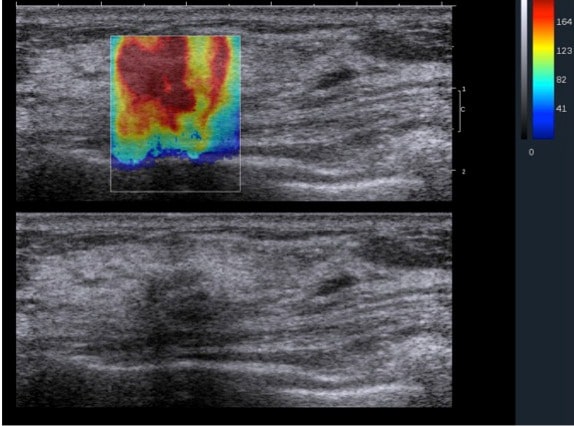

الاستوگرافی الاستوگرافی

• الاستوگرافی پستان